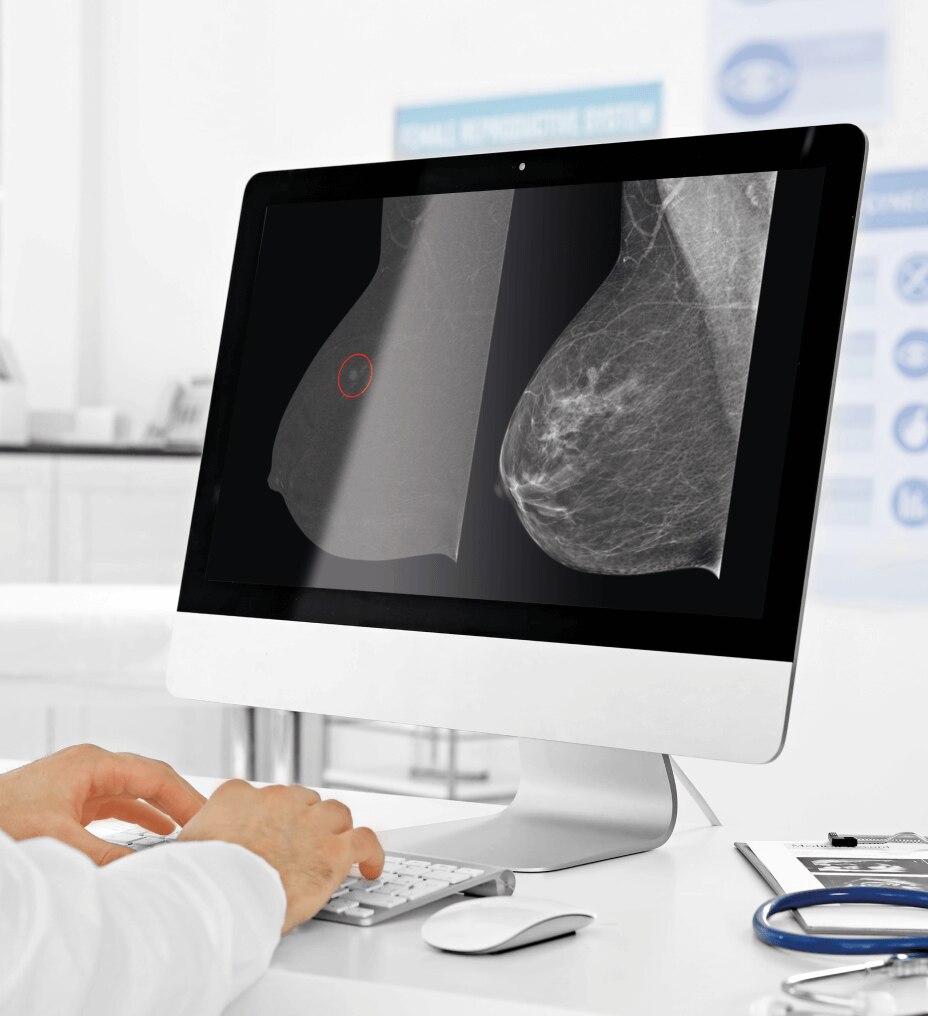

Immagini eccezionali

L'accesso ad AIR™ Recon DL consente una qualità delle immagini e una produttività eccezionali